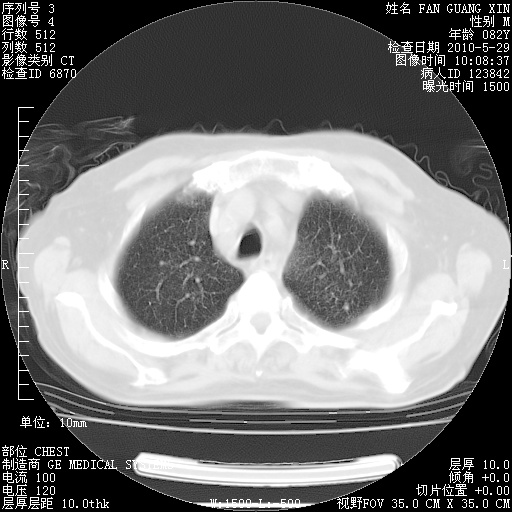

治疗3周后的肺部CT纵隔窗

再治疗10天后的肺部CT

阅读此次胸部CT,肺间质渗出性改变较入院时有吸收。目前从体温、白细胞、中性分叶明显增高,肯定存在细菌感染(发生医院感染哦,若无消化道及泌尿系统等感染的依据,肺部感染可能大)。若你院头孢哌酮舒巴坦钠耐药率较高,同意你的方案,若48小时体温仍高,可考虑使用碳青霉稀类抗菌药物,同时可予超声雾化、注意滴数时加大液体量。白蛋白33.30g/L较低哦,需加强营养等支持治疗。